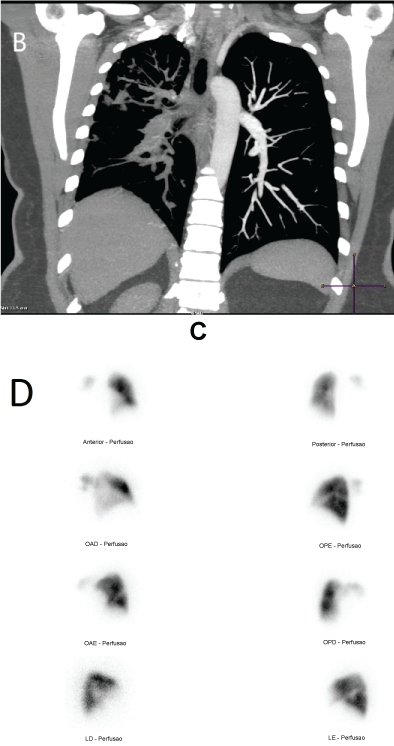

A 53-year-old female presented chronic dry cough and mild dyspnea, for 6 months. Due to an erroneous interpretation of CT findings (Figure 1A), she was diagnosed as pulmonary embolism, but without improvement with 6 months of anticoagulation. Evaluated at our service with progressive dyspnea, CTPA demonstrated complete occlusion of the right pulmonary artery (Figure 1A and Figure 1B). At echo, initial systolic pulmonary artery pressure 30 mmHg, not suggestive of pulmonary hypertension. A biopsy of the right pulmonary artery demonstrated the presence of choriocarcinoma. Chemotherapy was initiated with bleomycin, etoposide, cisplatin and, finally, dactinomycin. After treatment, patient remained asymptomatic, beta-HCG decreased from 198.374 mUI/ml to 1.8 mUI/ml. After a 5-year follow-up, neither return of the disease (Figure 1C), nor signs of pulmonary hypertension were characterized (normal echo and BNP), despite the vascular perfusion defect of the right lung on V/Q scan (Figure 1D). Pulmonary hypertension occurs when more than 60% of the lung vascular bed is impaired [1]. In this case, despite the sequel on right pulmonary artery at long-term, micro-vasculature is preserved. Therefore, right pulmonary artery occlusion is not enough, per se, to induce pulmonary hypertension. Up to this date, the patient is fine without specific pulmonary hypertension therapy and remains at clinical follow-up.

Figure 1A-B: Oncologic Right Pulmonary Artery Occlusion.

Figure 1C-D: Oncologic Right Pulmonary Artery Occlusion.